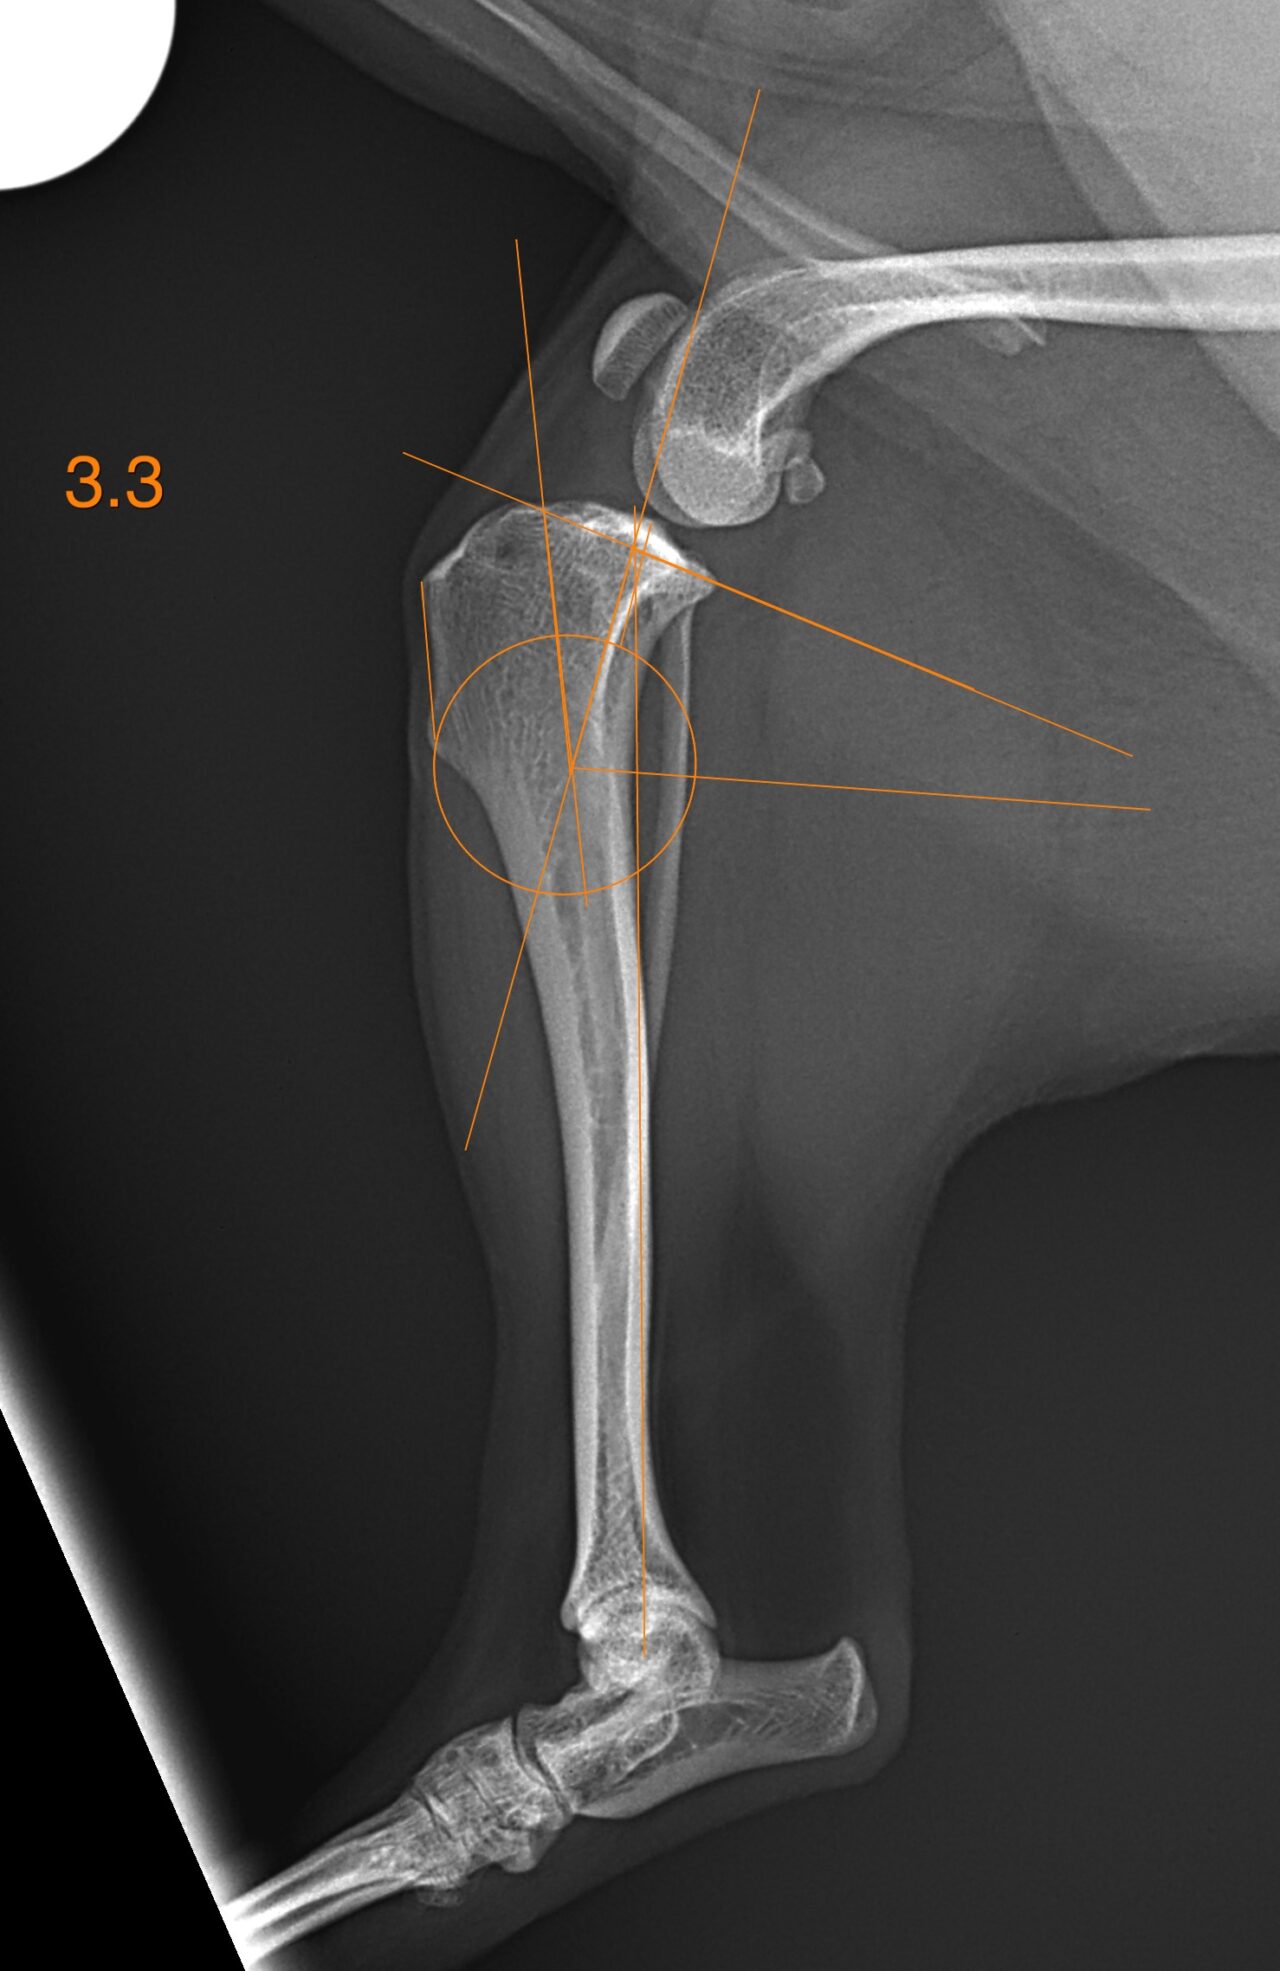

前十字靭帯断裂に対するCBLO #234 チワワの前十字靭帯断裂にCBLOで対応しました。骨切り部位の安定化にHCSとCBLOプレートを使用しています。しばらくは安静が必要です。 症例カテゴリー 放射線治療整形外科軟部組織外科脳神経外科内科腫瘍外科救急・集中治療リハビリテーション科腫瘍内科内視鏡科脳神経科呼吸器外科中医・漢方猫の腎移植循環器科